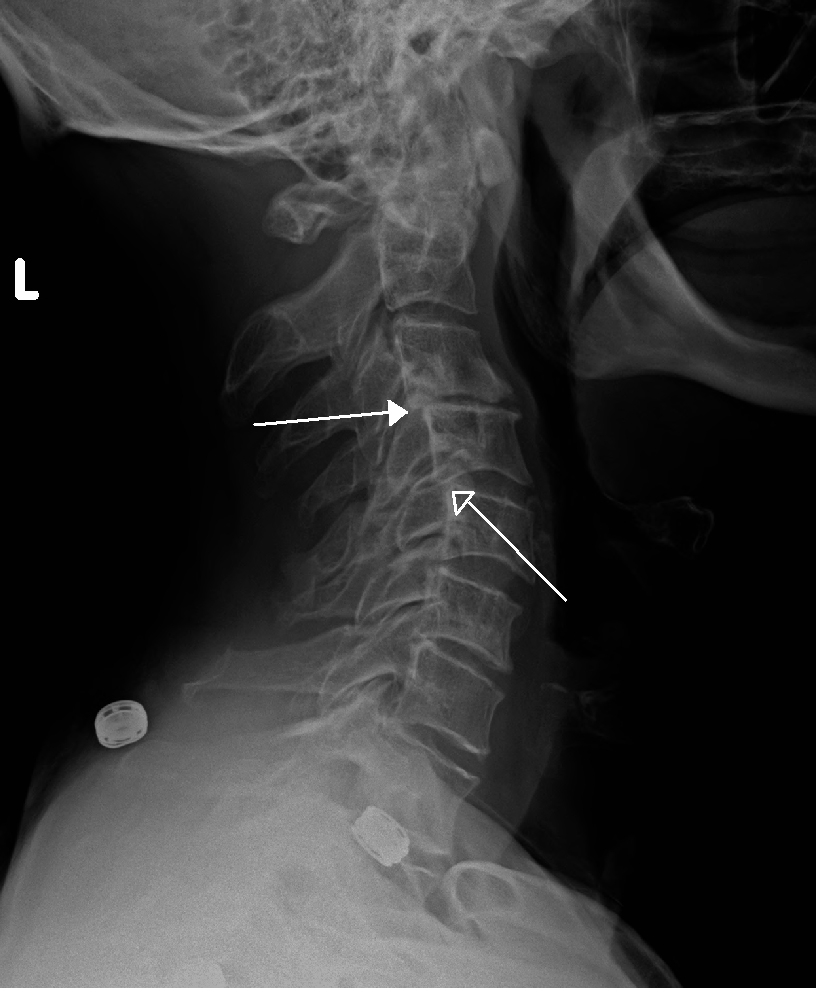

Neck Bone Spurs Xray – Treatment For Lower Back Pain Caused By Bone …

Neck Bone Spurs Xray – Treatment For Lower Back Pain Caused By Bone …

Spondylotic changes – cervical vertebrae – X-ray « PG Blazer